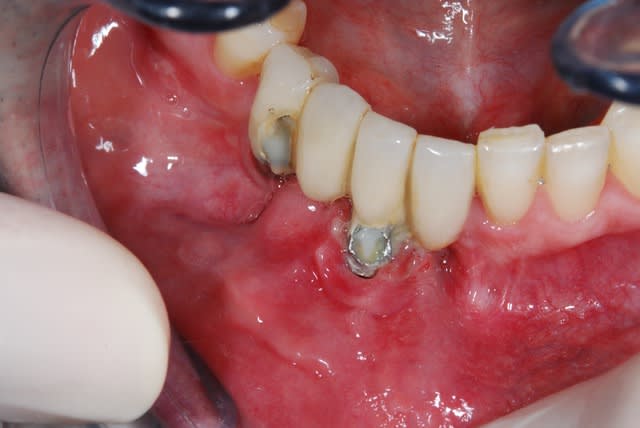

Patient de 33 ans venant pour une molaire douloureuse...

Je pense tenir le record du n'importe quoi implantaire.

là c'est moins marrant

les deux incisives adjacentes sont très mobiles et douloureuses,l'implant est en place depuis deux ans il y a du tartre de partout

solutions?